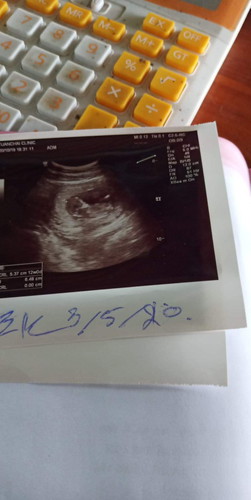

อ่านเพิ่มเติมเปนจร้าไปซาวได้12weekหมอบอกลูกดิ้นแล้วเพราะเห็นตอนซาวแอบตกใจยุว่าทำไมดิ้นเรวจังเพราะคนแรกไม่เคยได้ดูเลยคะคนสองนี่ฝากคลินิคได้ดูตลอดหมอบอกดิ้นแล้วแต่แม่ยังไม่รุ้สึก จะรุ้สึกจริงๆตอน4-5เดือนคะ แอบเห็นลูกโบกมือให้ด้วย🥰🥰🥰

12wแล้วจร้า ดิ้นเก่งมากแต่แม่ไม่รู้สึกเลยแค่เห็นลูกแข็งแรงก็มีความสุขแล้วจร้า